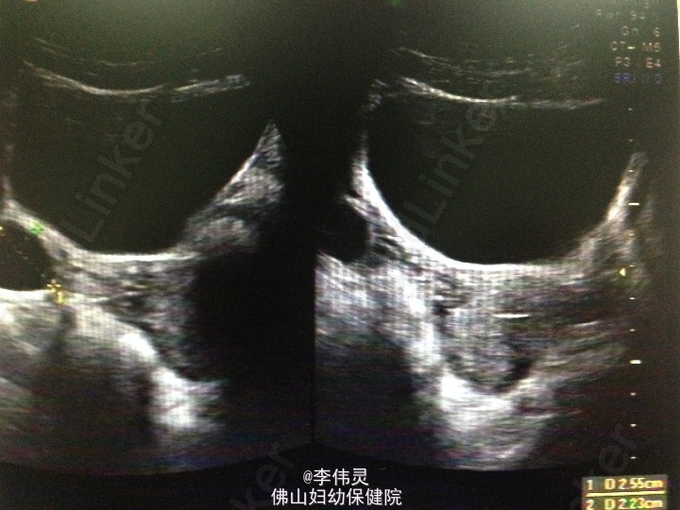

患者因“葡萄胎清宫术后20天。”入院。未婚未孕女性,孕1产0.曾因“葡萄胎?”在外院行3次清宫术,术后病理示部分性葡萄胎。术后定期检测血糖HCG,5月19日血HCG下降至11327.27mIU/ml,后5月20日外院复查血HCG:25799IU/l,查B超示:宫腔上段见一稍高强回声光团,大小约3×2.7×2.9cm,与肌层分界不清,内部回声不均,考虑妊娠滋养细胞疾病未除。

查体:生命体征平稳,心肺未见明显异常。双下肢无水肿。 辅助检查:HCG 34543IU/l。肝功能:ALT94IU/L,AST 53 IU/L,GGT 43 IU/L,TBA 36 umol/L。B超:子宫正常大小,宫腔上段见一稍高强回声光团,大小约3×2.7×2.9cm,与肌层分界不清,内部回声不均,考虑妊娠滋养细胞疾病未除。右侧宫旁囊性包块,囊肿未除。余未见明显异常。